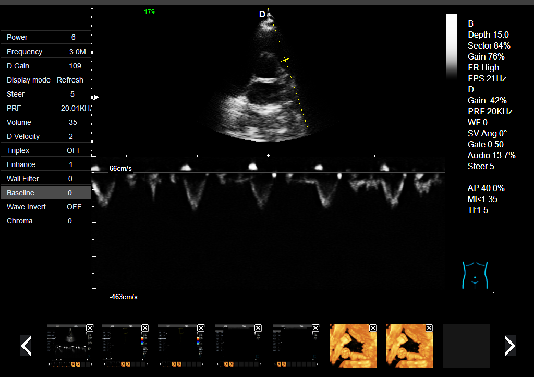

P5-VET便攜式獸用彩超機

P5-VET便攜手提式獸用彩超機

全數字彩色動物超聲診斷儀

彩色多普勒動物寵物超聲診斷儀

P5-VET獸用彩超機出色的獸用臨床應用

P5-VET高清便攜式獸用彩超機是一款高清晰度,功能全面的彩色多普勒獸用超聲診斷儀,它可以滿足滿足寵物醫院及科研機構在消化系統、生殖系統、泌尿系統、體檢及其它方面的檢查和診斷。